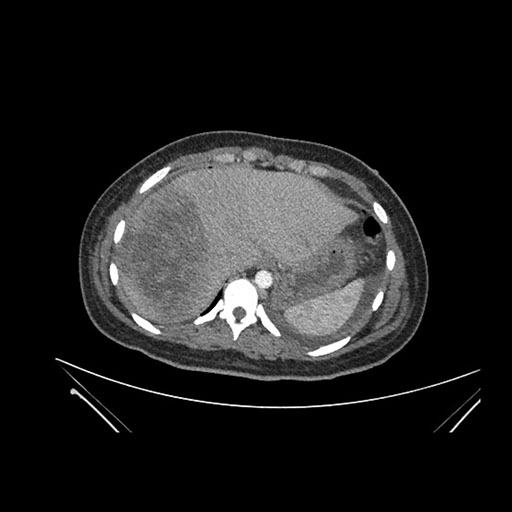

Axial Arterial

Axial Venous